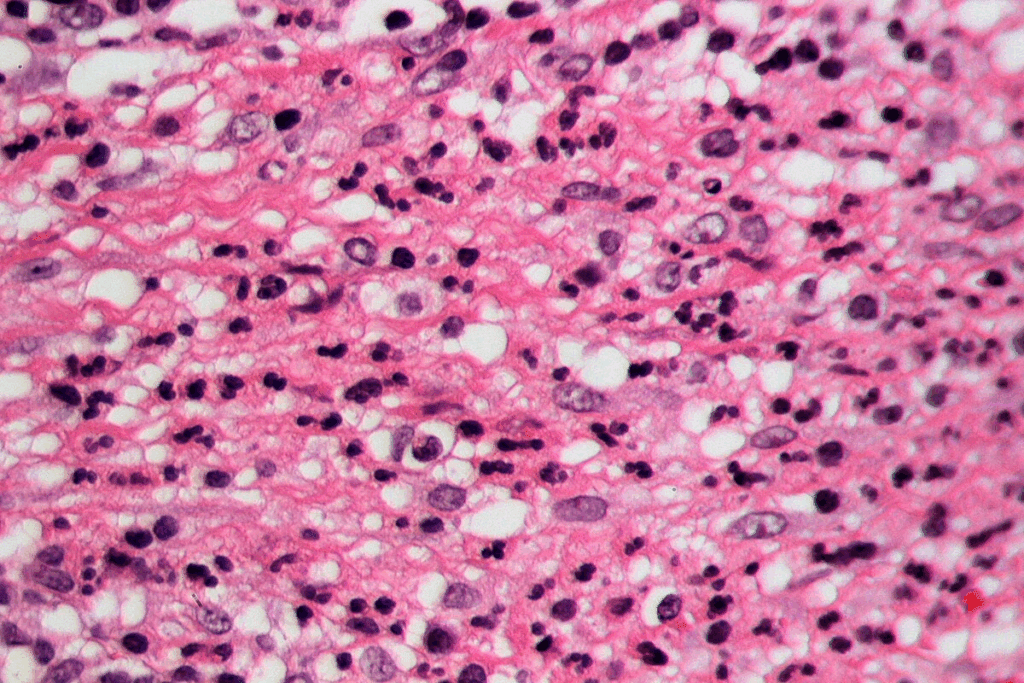

Bacterial Infections and Common Pathogens

Bacterial infections are the main cause of peritonsillar abscess. Group A beta-hemolytic streptococcus is the most common bacteria. Other bacteria like Staphylococcus aureus and anaerobic bacteria can also cause it. These bacteria infect the tonsils and the area around them, leading to an abscess.